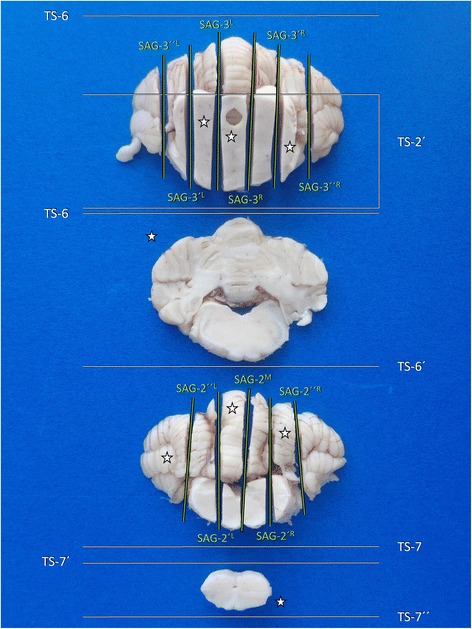

Figure 17 provides a summary of the possible tissue slabs generated through the described protocol for tissue block C trimming (Table 9).

Fig. 17.

Overview of main brain slabs of Block C in correct angle of section. A selection of these may be further processed for histology. Asterisks mark our recommendation for systematic epilepsy pathology studies